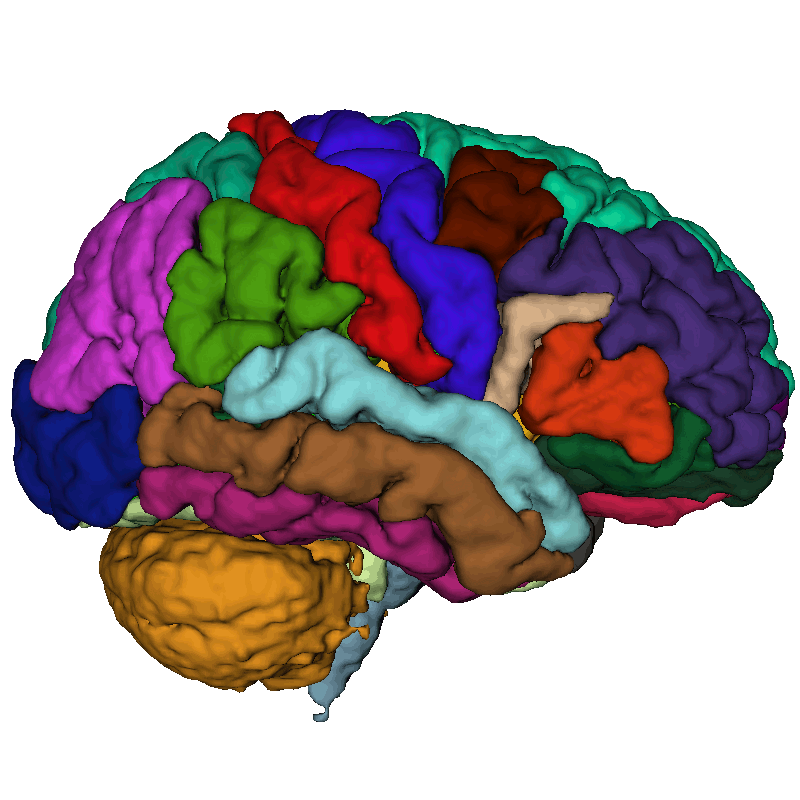

02 Parcellation

07 Masking

Future enhancement

Automatic creation of ROIs for tractographies